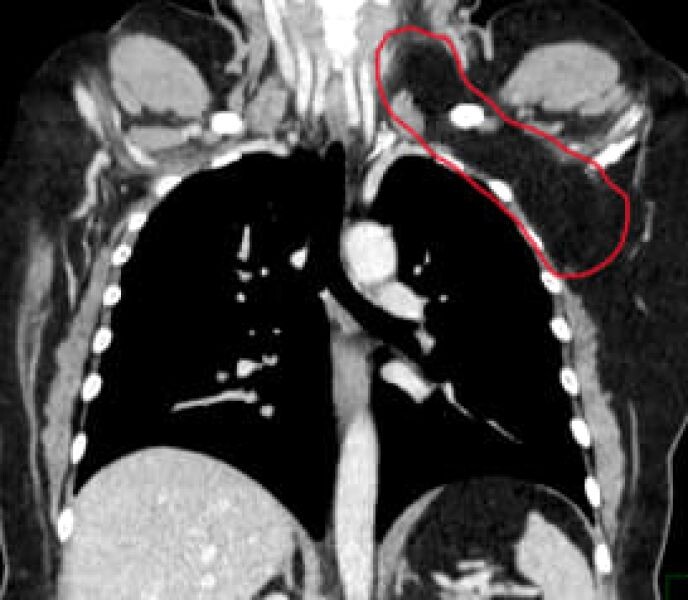

У горожанки было подозрение на рак Опухоль размером с дыню, 20 х 15 сантиметров, удалили воронежанке, сообщил региональный Минздрав. 50-летняя женщина обратилась к медикам в онкоцентр, когда заметила новообразование в области левой надключичной ямки. Опухоль начала расти и доставляла дискомфорт. Сначала горожанке поставили страшный диагноз — рак, липосаркома. К счастью, при дальнейших исследованиях вердикт не подтвердился. Выяснилось, что опухоль доброкачественная, липома. Она формируется из патологически разрастающейся жировой ткани. Новообразование занимало две области организма, надключичную и грудную, а также окутывала жизненно-важные структуры. Команда медиков во главе с кандидатом медцинских наук Михаилом Фонштейном провела сложную операцию и вырезала опухоль. Сейчас женщина идёт на поправку и чувствует себя хорошо.

Опухоль размером с дыню, 20 х 15 сантиметров, удалили воронежанке, сообщил региональный Минздрав.

50-летняя женщина обратилась к медикам в онкоцентр, когда заметила новообразование в области левой надключичной ямки. Опухоль начала расти и доставляла дискомфорт.

Сначала горожанке поставили страшный диагноз — рак, липосаркома. К счастью, при дальнейших исследованиях вердикт не подтвердился. Выяснилось, что опухоль доброкачественная, липома. Она формируется из патологически разрастающейся жировой ткани.

Новообразование занимало две области организма, надключичную и грудную, а также окутывала жизненно-важные структуры. Команда медиков во главе с кандидатом медцинских наук Михаилом Фонштейном провела сложную операцию и вырезала опухоль.